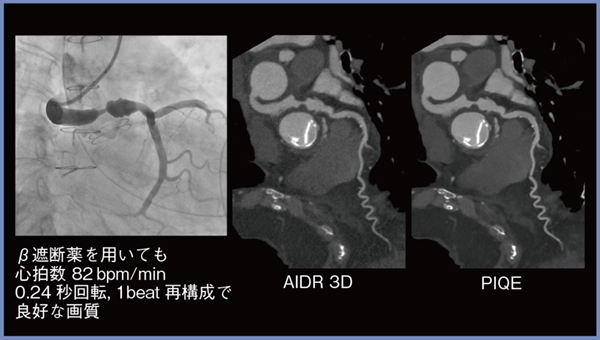

Aquilion ONE / INSIGHT Editionでは,ガントリの回転速度が,同社従来CTの0.275s/rotから0.24s/rotに高速化している。そのため,高心拍の症例においても,冠動脈が明瞭に描出される。

図3は大動脈基部置換(Bentall)術後の症例である。β遮断薬を使用してもHR:82bpmと高心拍であったが,0.24s/rotの1beat再構成によって良好な画質が得られた。

図3 高心拍症例(0.24s/rot 1beat撮影)